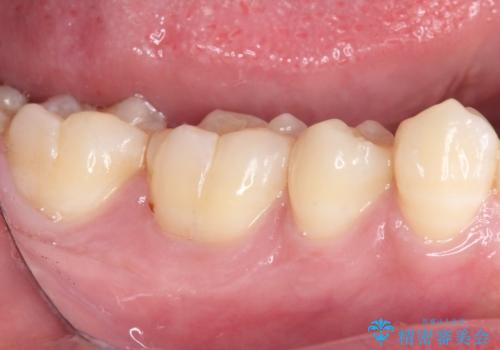

- 右下の奥歯が噛んだ時に痛み、冷たいものがしみることを主訴として来院された患者様です。

精査の結果、歯が欠けていてその下に虫歯が認められました。

また、咬合面(歯の噛む面)に以前治療した樹脂の詰め物があるため、一度外して虫歯を完全に除去し、

精度の高いセラミックインレーにて修復処置することとしました。

噛んだ時の痛みや、冷たいものがしみる症状はなくなり、見た目も自然でどこが詰め物かわからないと、患者様は大変満足されました。